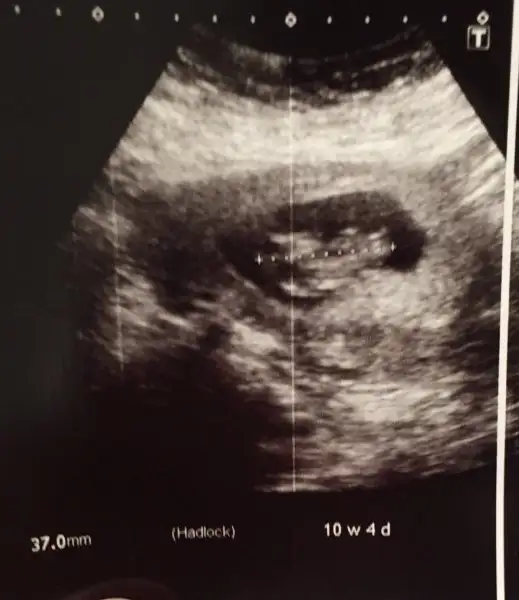

10 haftada ki görüntümüz ama bu hafta da nub oluşmuş oluyor mu ayy buraya baktıkça daha çok merak saldım

10 haftada ki görüntümüz ama bu hafta da nub oluşmuş oluyor mu ayy buraya baktıkça daha çok merak saldımKız gördüm ben de :) sağlıkla gelsin kuzucuk :)